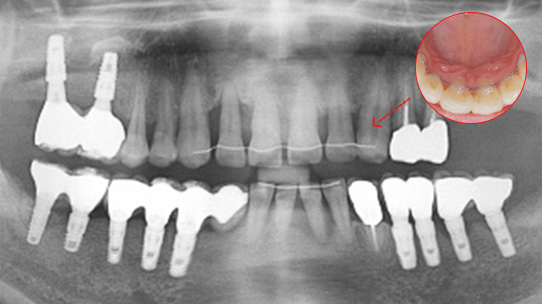

심한 염증과 기존 보철물의 오염상태가 심해 다른 병원에서 임플란트 17개 진단을 받고 내원, 특히 앞니부분의 치조골이 많이 약해져 흔들림이 심하여 바로 치주치료를 시행하였습니다. 치주치료 2주 후 앞니 잇몸이 개선되어 발치 하지 않고 교정 유지장치를 이용하여 흔들림을 보완하였습니다. 오염된 보철물을 제거하고 임플란트 11개를 식립하였습니다.

심한 염증으로 치아가 흔들리는 상태

앞니 흔들림을 보완하는 유지장치 부착